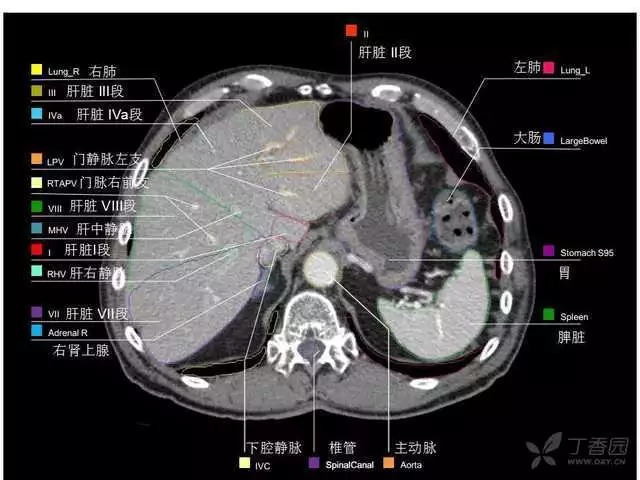

腹部肝脏高清CT断层的图谱

全腹部高清CT图谱,淋巴结彩色图谱,血管解剖图谱大汇总!

肝段,肝内管道的分布规律